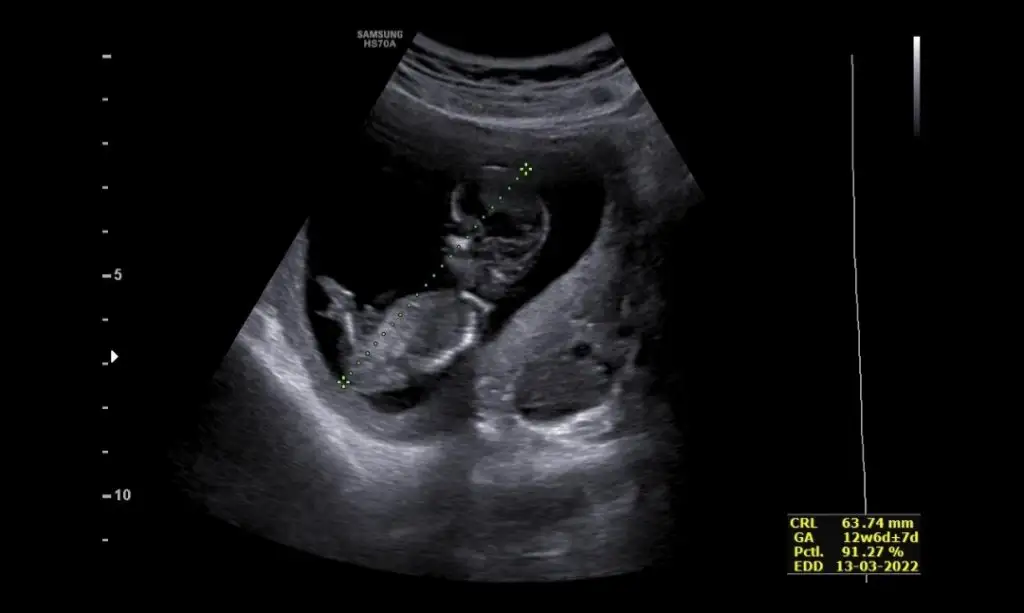

Net değil USG emin olamadımIkra meyra bu görüntümüz var ama sırtı dönük tahmin yapabilecek misin bu ultrasonda canım teşekkürler

Emin olamadım sanki erkek gibi

Doktor da emin değil ama erkek gibi sanki dediEmin olamadım sanki erkek gibi